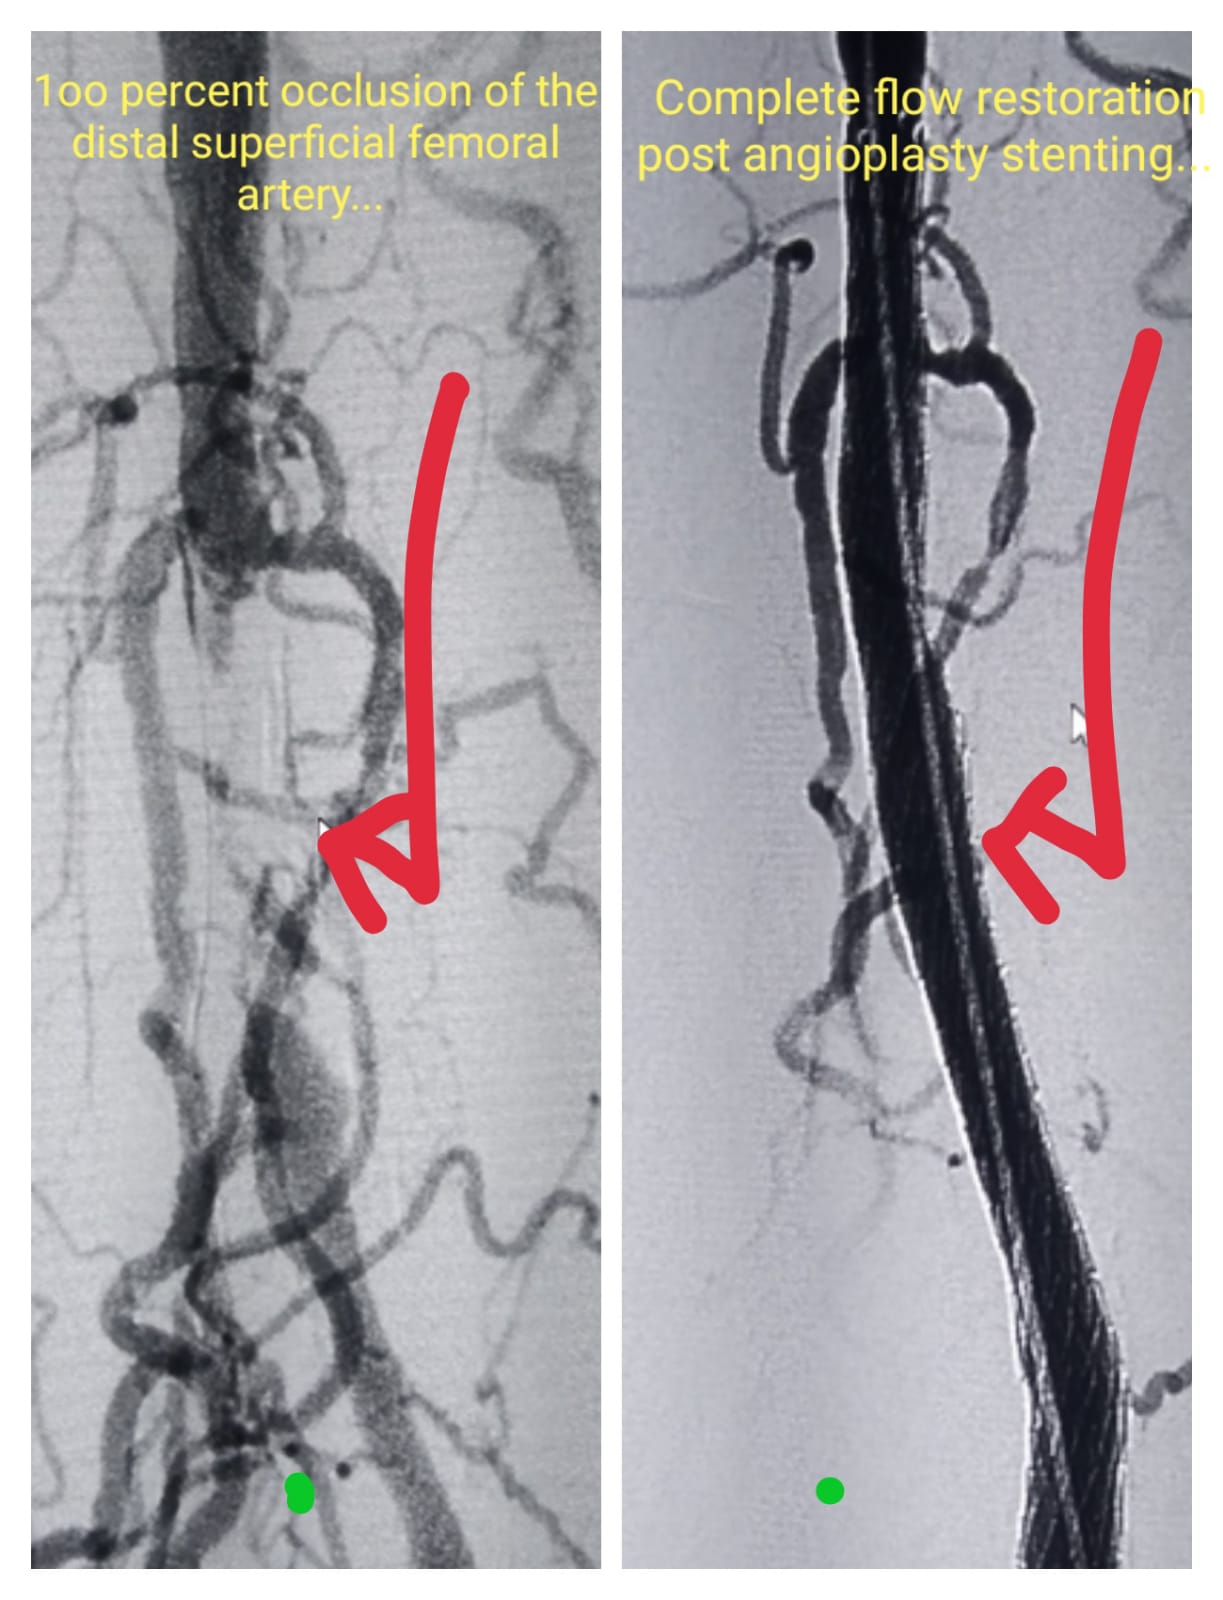

Superficial Artery stenting- Pre Procedure & Complet blood flow restoration post stenting

Angioplasty- Pre and Post